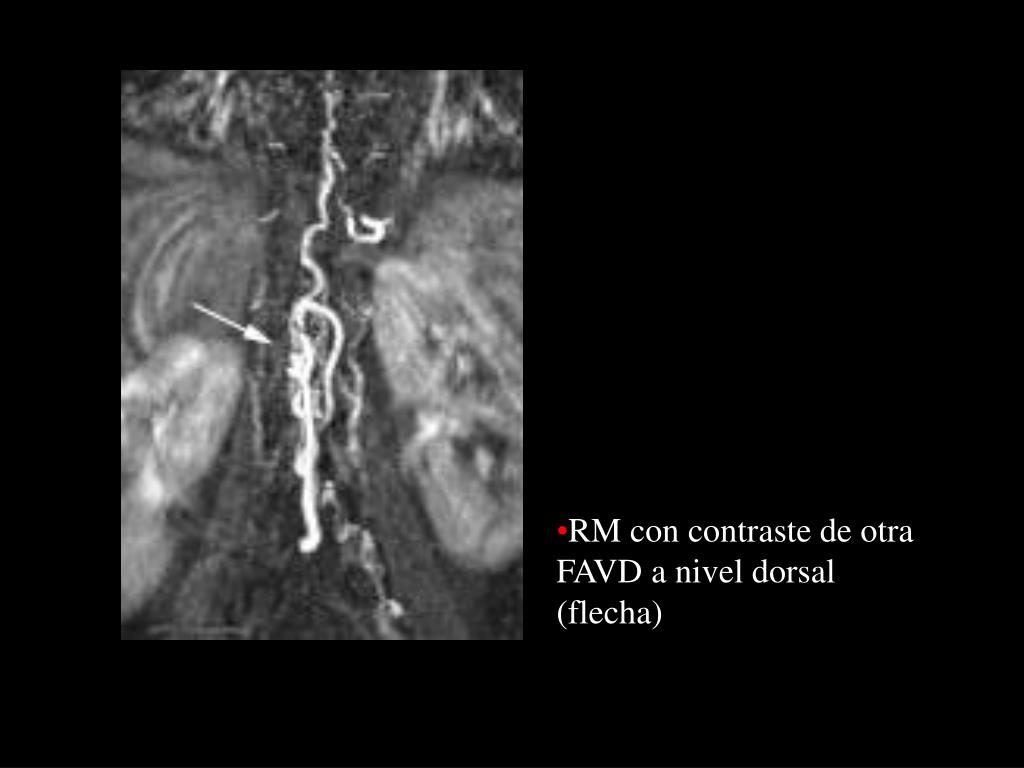

4. RM con contraste de otra FAVD a nivel dorsal (flecha)